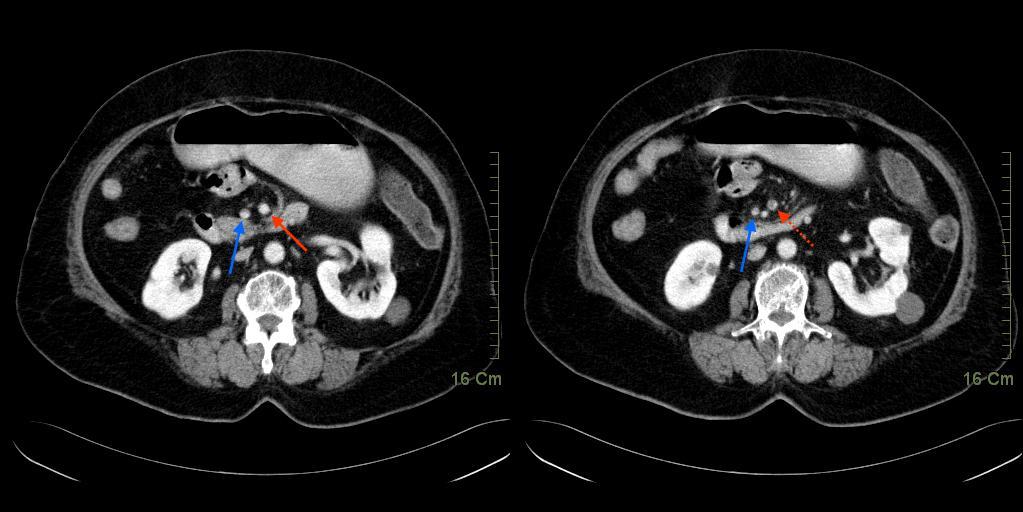

這是位老太太的腹部電腦斷層,看倌兒可以回想咱們提過的,男生女生大不同,便可分辨。

這是老太太腹痛發作不多時的片子。箭頭指出來,腹部中央兩個圓滾滾,便是上腸系膜動脈(SMA,紅箭頭)及上腸系膜靜脈(SMV,藍箭頭)。稍稍比較紅虛線和紅實線,可以清楚見到紅虛線這邊的血管裡多了個陰影,這便是塞住血管的血栓。這個血栓還惡霸霸地卡在上腸系膜動脈相當主幹的位置。